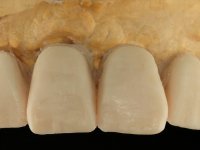

O paciente foi observado conjuntamente e a dúvida que surgiu de imediato foi se seria possível com a regeneração óssea a efectuar poder ser reabilitada naturalmente a zona das papilas interdentárias. Nesse sentido foi feito um enceramento de diagnóstico que contemplaria as duas hipóteses, utilizando ou não a cerâmica gengival. A confecção desse enceramento foi fundamental para expor ao paciente a dificuldade da reabilitação. O wax-up deu origem a um mock-up que foi aprovado pelo paciente e que simultaneamente serviu de guia imagiológica. O caso foi planificado cirurgicamente e realizada uma guia cirúrgica com que foram colocados os implantes. Após 10 semanas foi feita a 1ª impressão para confecção da ponte provisória. Foram criados os primeiros perfis de emergência na gengiva artificial e foi digitalizado o modelo. Por processo de CAD-CAM foi confeccionada uma ponte provisória aparafusada baseada no enceramento de diagnóstico. A ponte trabalhou durante 8 semanas os tecidos moles que foram fielmente copiados numa impressão com técnica de moldeira aberta. Os transferes foram individualizados com resina composta para copiarem fielmente os perfis de emergência criados pela ponte provisória. Confeccionado o modelo de trabalho definitivo, foi realizada uma infra-estrutura em zircónio seguindo a orientação do enceramento de diagnóstico. O assentamento da infra-estrutura foi testado em boca e simultaneamente foi novamente impressionados os tecidos moles com um silicone fluido. Nessa consulta foi feito o levantamento da cor. Os dentes 13 e 23 apresentavam uma saturação anormalmente forte que resolvemos não valorizar, optando por privilegiar a relação com o sector antero-inferior. Foi realizada uma nova gengiva artificial com a impressão que acompanhou a impressão de arrasto com a infra-estrutura. Após a colocação da cerâmica na infra-estrutura foram coladas as meso-estruturas. O trabalho final foi aparafusado lentamente permitindo a adaptação dos tecidos moles.